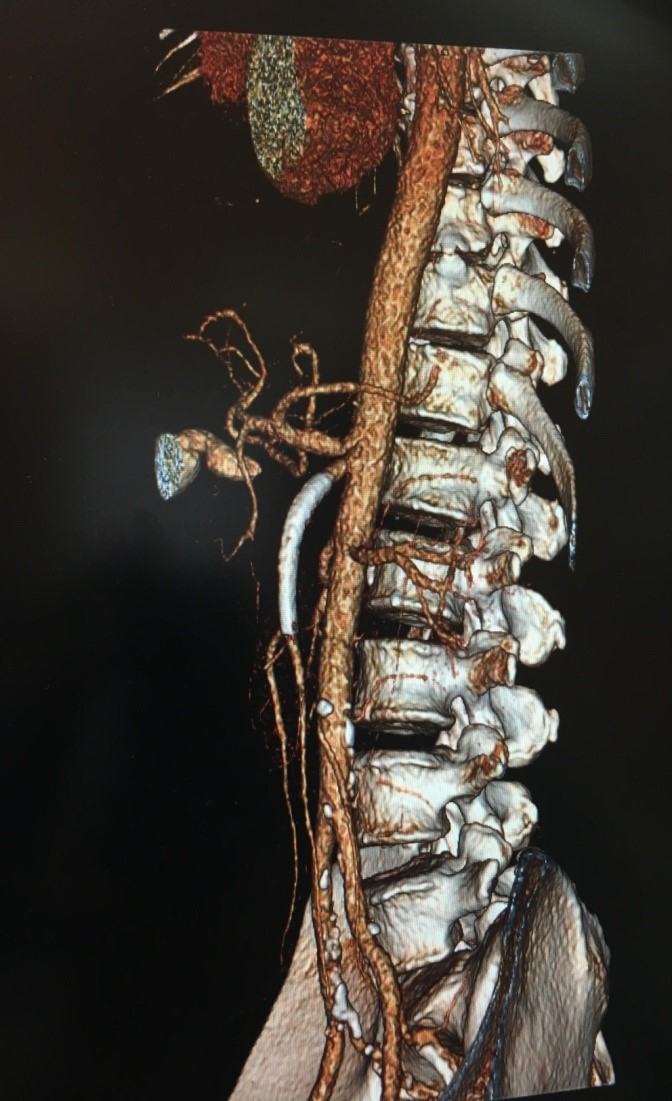

Через сутки после операции, выполнена компьютерная томография органов брюшной полости и забрюшинного пространства с внутривенным болюсным контрастированием: стент в БВА проходим, дистальные отделы ВБА проходимы (рис. 6). Тромбоз дистальных отделов селезеночной артерии. Инфаркт селезенки.

Рисунок 6. МСКТ ангиография, стрелкой показан стент ВБА.